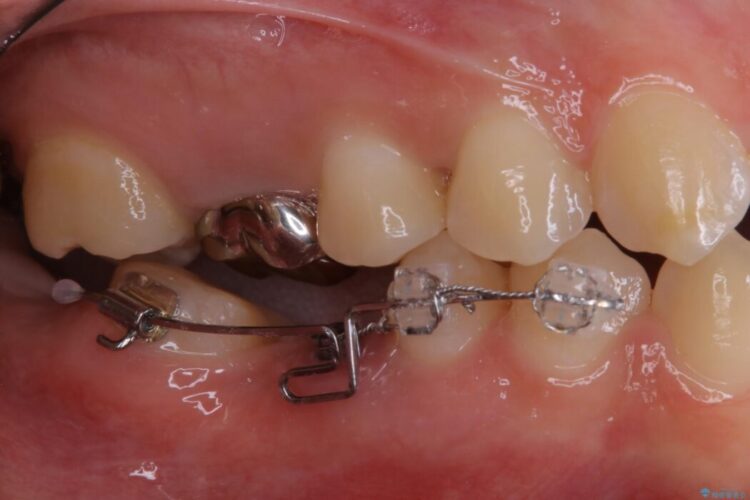

この状態のままブリッジ治療へと進んでしまうと神経が露出する可能性が否定できないため、まずワイヤー装置による部分矯正で歯軸を通常位置へ戻してから補綴治療を行うこととしました。

本症例では、健康な歯を可及的に守るため神経の処置を避けた上で部分矯正を併用して行うことにより、安全に補綴治療(ブリッジ)ができました。